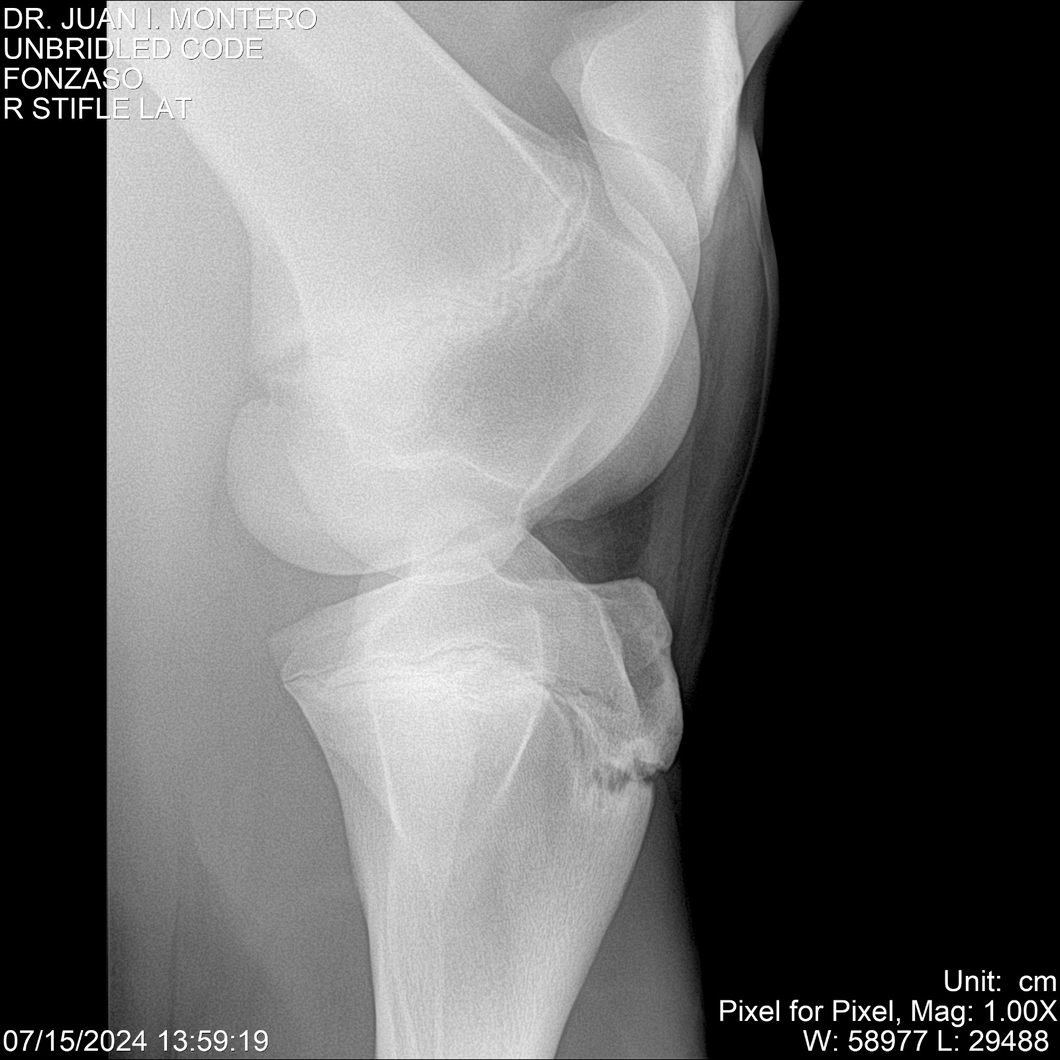

• Empresa: Abelenda N. R., Walter Hugo